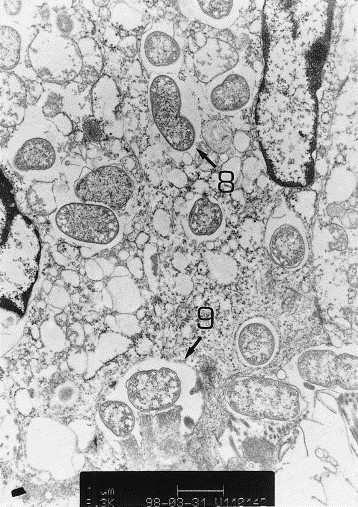

Histological and ultrastructural lesions present in the gut. A. Light micrograph of descending colon of calf 3. Bacteria attached to the top of the enterocytes (1), presence of lymphocyte and polymorphonuclear leucocytes (2), and area without bacteria (3). The bar corresponds to 25 μm. B. Scanning electron microscopy of spiral colon of calf 2: microvilli effacement is clearly visible (4) as are bacteria attached to the top of the microvilli (5). The bar corresponds to 10μm. C. Transmission electron microscopy of the spiral colon of calf 2: bacteria adhere to the enterocyte cytoplasmic membrane (6); pedestal and actin accumulation (7) are clearly visible. The bar corresponds to1μm. D. Transmission electron microscopy of the ileum of calf 2: bacteria internalization (8) and a pedestal-bacteria complex in a phagosome (9) are visible inside of the enterocyte.

Scanning and electron microscopy confirmed the presence of closely adherent bacteria and of localized effacement of the enterocyte microvilli where the bacteria attached (figure 2B, 2C). Pedestal and actin accumulation under the zone of adherence of the bacteria were also present (figure 2C). Moreover, internalization into the enterocytes of bacteria and of bacteria-pedestal complexes were evident in calf 2 (figure 2D). None of these lesions were observed in the control calf.

An often overlooked property of at least some EPEC/EHEC strains is their capacity to invade cells in vitro [8] and in vivo [28]. Internalization of bacteria and also of bacteria-pedestal complex inside the enterocyte was observed in two of the three calves (table II). It is also worth noting that strain 340S89, and several other EHEC and EPEC bovine strains, give images of internalization into the enterocytes when tested in the rabbit ligated intestinal loop assay [4], [12]. The significance of this stage is unknown but may be related to the invasion of the calf by the bacteria. Indeed, the challenge strain was isolated from the mesenteric lymph nodes of the same two calves. However the challenge strain was never detected in other organs or in heart blood.